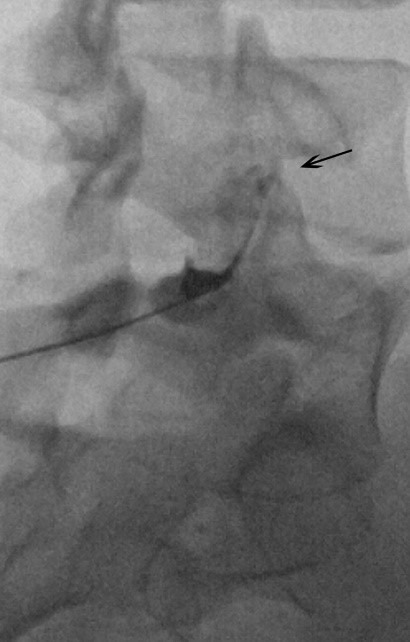

ابتدا محل ورود سوزن با مالیدن موادی تمیز و استریل می شود. سپس با تزریق داروی بی حسی در محل ورود سوزن آن محل بی حس می شود. سپس سوزن مخصوص با کمک دستگاه فلوروسکوپی به محل مورد نظر هدایت می گردد. با ورود سوزن تا رسیدن آن به مفصل عکس های متعدد رادیولوژی گرفته می شود تا اطمینان حاصل شود که سوزن به محل لازم رسیده است. وقتی سوزن به محل مورد نظر رسید ابتدا مقدار کمی ماده حاجب رادیولوژی تزریق می شود تا قرار گیری سوزن در داخل مفصل فست قطعا تایید گردد.

سپس داروی کورتیکواستروئید و بی حس کننده موضعی به آرامی به محل مفصل تزریق می گردد. معمولا کل این فرایند بین 15 تا 20 دقیقه به طول خواهد انجامید. تزریق فست می تواند در خود مفصل باشد که در بالا توضیح داده شد یا در اطراف اعصابی که پیامهای درد را از فست به مغز می برند که به آن بلوک فست می گویند.